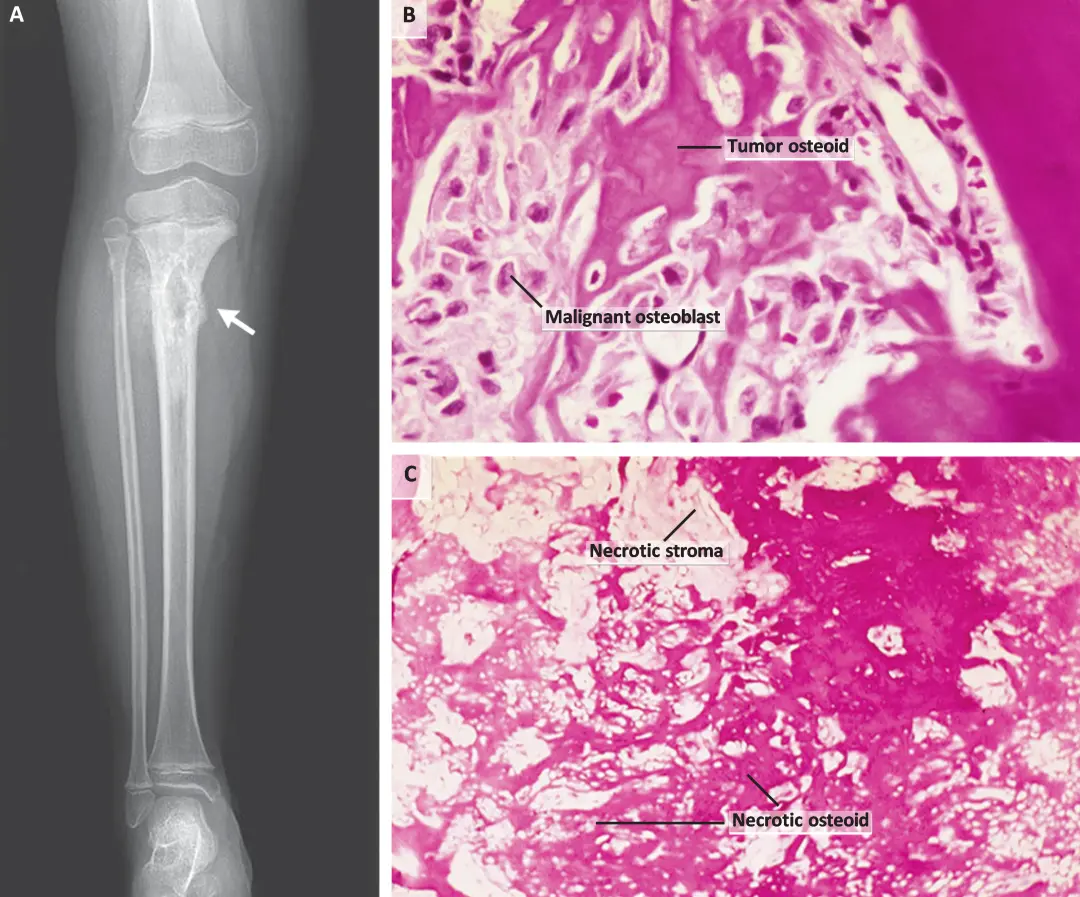

分期与预后

大多数患者表现出反复的骨痛症状,而进一步通过放射性检查提示存在骨肉瘤的可能性(图1a)。通过活检进行诊断(图1B)。肿瘤分期有助于手术治疗和预后。肌肉骨骼肿瘤学会(MSTS)和美国癌症联合委员会-国际抗癌联盟(AJCC-UICC)的分期系统是使用最广泛的。1980年采用的MSTS系统基于肿瘤分级和发病部位。大多数患者处于IIB期骨肉瘤,其特征是高分化组织学特征,通过骨皮质延伸至骨膜,无转移。较新的AJCC-UICC分期系统使用肿瘤—淋巴结—转移(TNM)分期,但也包括肿瘤分级。无论采用哪种分期系统,大多数肿瘤都是直径为小于等于8cm且无转移的高级别肿瘤,在AJCC-UICC分期系统中为IIA期,在MSTS系统中为IIB期。治疗非依赖性和治疗相关的因素都会影响预后。在一项涉及 2260 名高级别骨肉瘤患者的研究中,与不良预后最密切相关的治疗前因素是转移的存在和轴向骨的位置。导致生存率较差的治疗后因素包括手术切除不完整和化疗反应不佳。

图1 骨肉瘤治疗前后的影像学特征和组织学特征。

【在图A中,右腿的x光片显示胫骨近端有侵袭性骨病变,伴有骨膜反应(箭头)。在图B中,开始治疗前骨肉瘤肿瘤的苏木精和伊红染色显示恶性多形性成骨细胞和恶性肿瘤类骨细胞。在图C中,新辅助治疗10周后切除肿瘤的苏木精和伊红染色显示良好的反应,坏死率超过90%。】

骨肉瘤的主要治疗方法是原发肿瘤的手术切除,这最初是通过根治性切除(截肢)来完成的。20世纪70年代与骨肉瘤全身治疗同时出现的保肢手术,现已用于90%的患者。保肢手术包括完全切除肿瘤,及接下来的骨骼和软组织重建。新辅助疗法提供了评估在病灶原位处化疗效果的机会,即通过检查切除标本中治疗诱导坏死的量(图1B和1C)。反应评估为良好(≥90% 坏死)或差(<90% 坏死)。经过10至12周的标准新辅助治疗后,约55%的患者有良好反应,5年生存率约为75%。对于那些反应差的人,5年生存率约为45%,这仍大大超过了常规使用化疗前的生存率。虽然一项随机研究对比了新辅助治疗与术后辅助化疗,结果并未显示出显著的差异,但术前(或新辅助)化疗现在已经是标准做法。